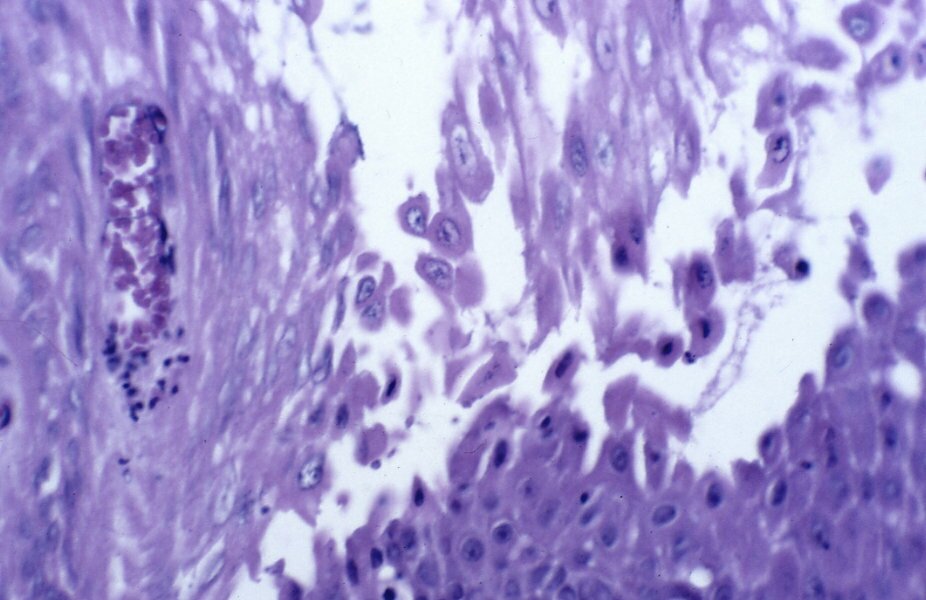

L'examen clinique ne retrouvait pas d'autres l?sions cutan?es, ni d'atteinte muqueuse et des ongles. L'examen histologique d'un pr?l?vement cutan? objectivait une acantholyse aboutissant ? la constitution d'une bulle intra ?pidermique. L'immunofluorescence directe montrait des d?p?ts d'IgG au niveau des espaces intercellulaires de l'?piderme. Le bilan biologique ?tait normal. La recherche d'anticorps anti espace intercellulaire ?tait n?gative. L'immunoblot n'?tait pas r?alis?. Le diagnostic retenu ?tait celui de pemphigus vulgaire localis? sur cicatrice de br?lure. La patiente ?tait trait?e par Clob?tasol (Dermoval?) pendant 3 mois puis par dapsone 100 mg/J (Disulone?) sans am?lioration. Un traitement par prednisone (Cortancyl?) ? 1mg/kg/j ?tait introduit entra?nant une am?lioration transitoire. La posologie de la prednisone ?tait augment?e ? 1,5 mg/kg/j puis ? 2 mg/kg/j. L '?volution ?tait favorable. Avec un recul de 6 mois, nous n'avons pas not? de r?cidive.